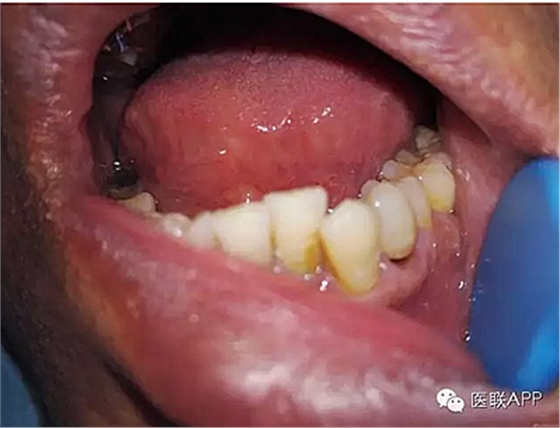

34頰側(cè)楔狀缺損達(dá)髓腔,可探及穿髓孔,探痛(-),叩痛(+),松動(dòng)I度。

1、楔狀缺損是小病,但是不重視也可以導(dǎo)致牙髓炎、根尖周炎,很多時(shí)候隱匿的楔狀缺損不易發(fā)現(xiàn),引不起患者的重視,等到發(fā)現(xiàn)的時(shí)候已經(jīng)根尖周炎。